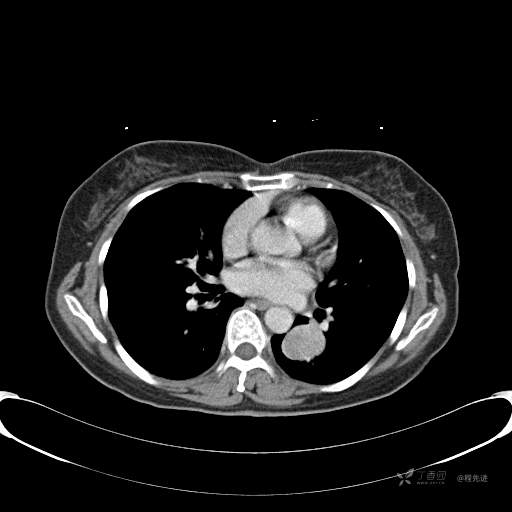

患者性别:女

患者年龄:57岁

简要病史:体检发现

CT增强

平扫CT值约40HU(未上传图像),增强后动脉期CT值约70HU,静脉期CT值约97HU。